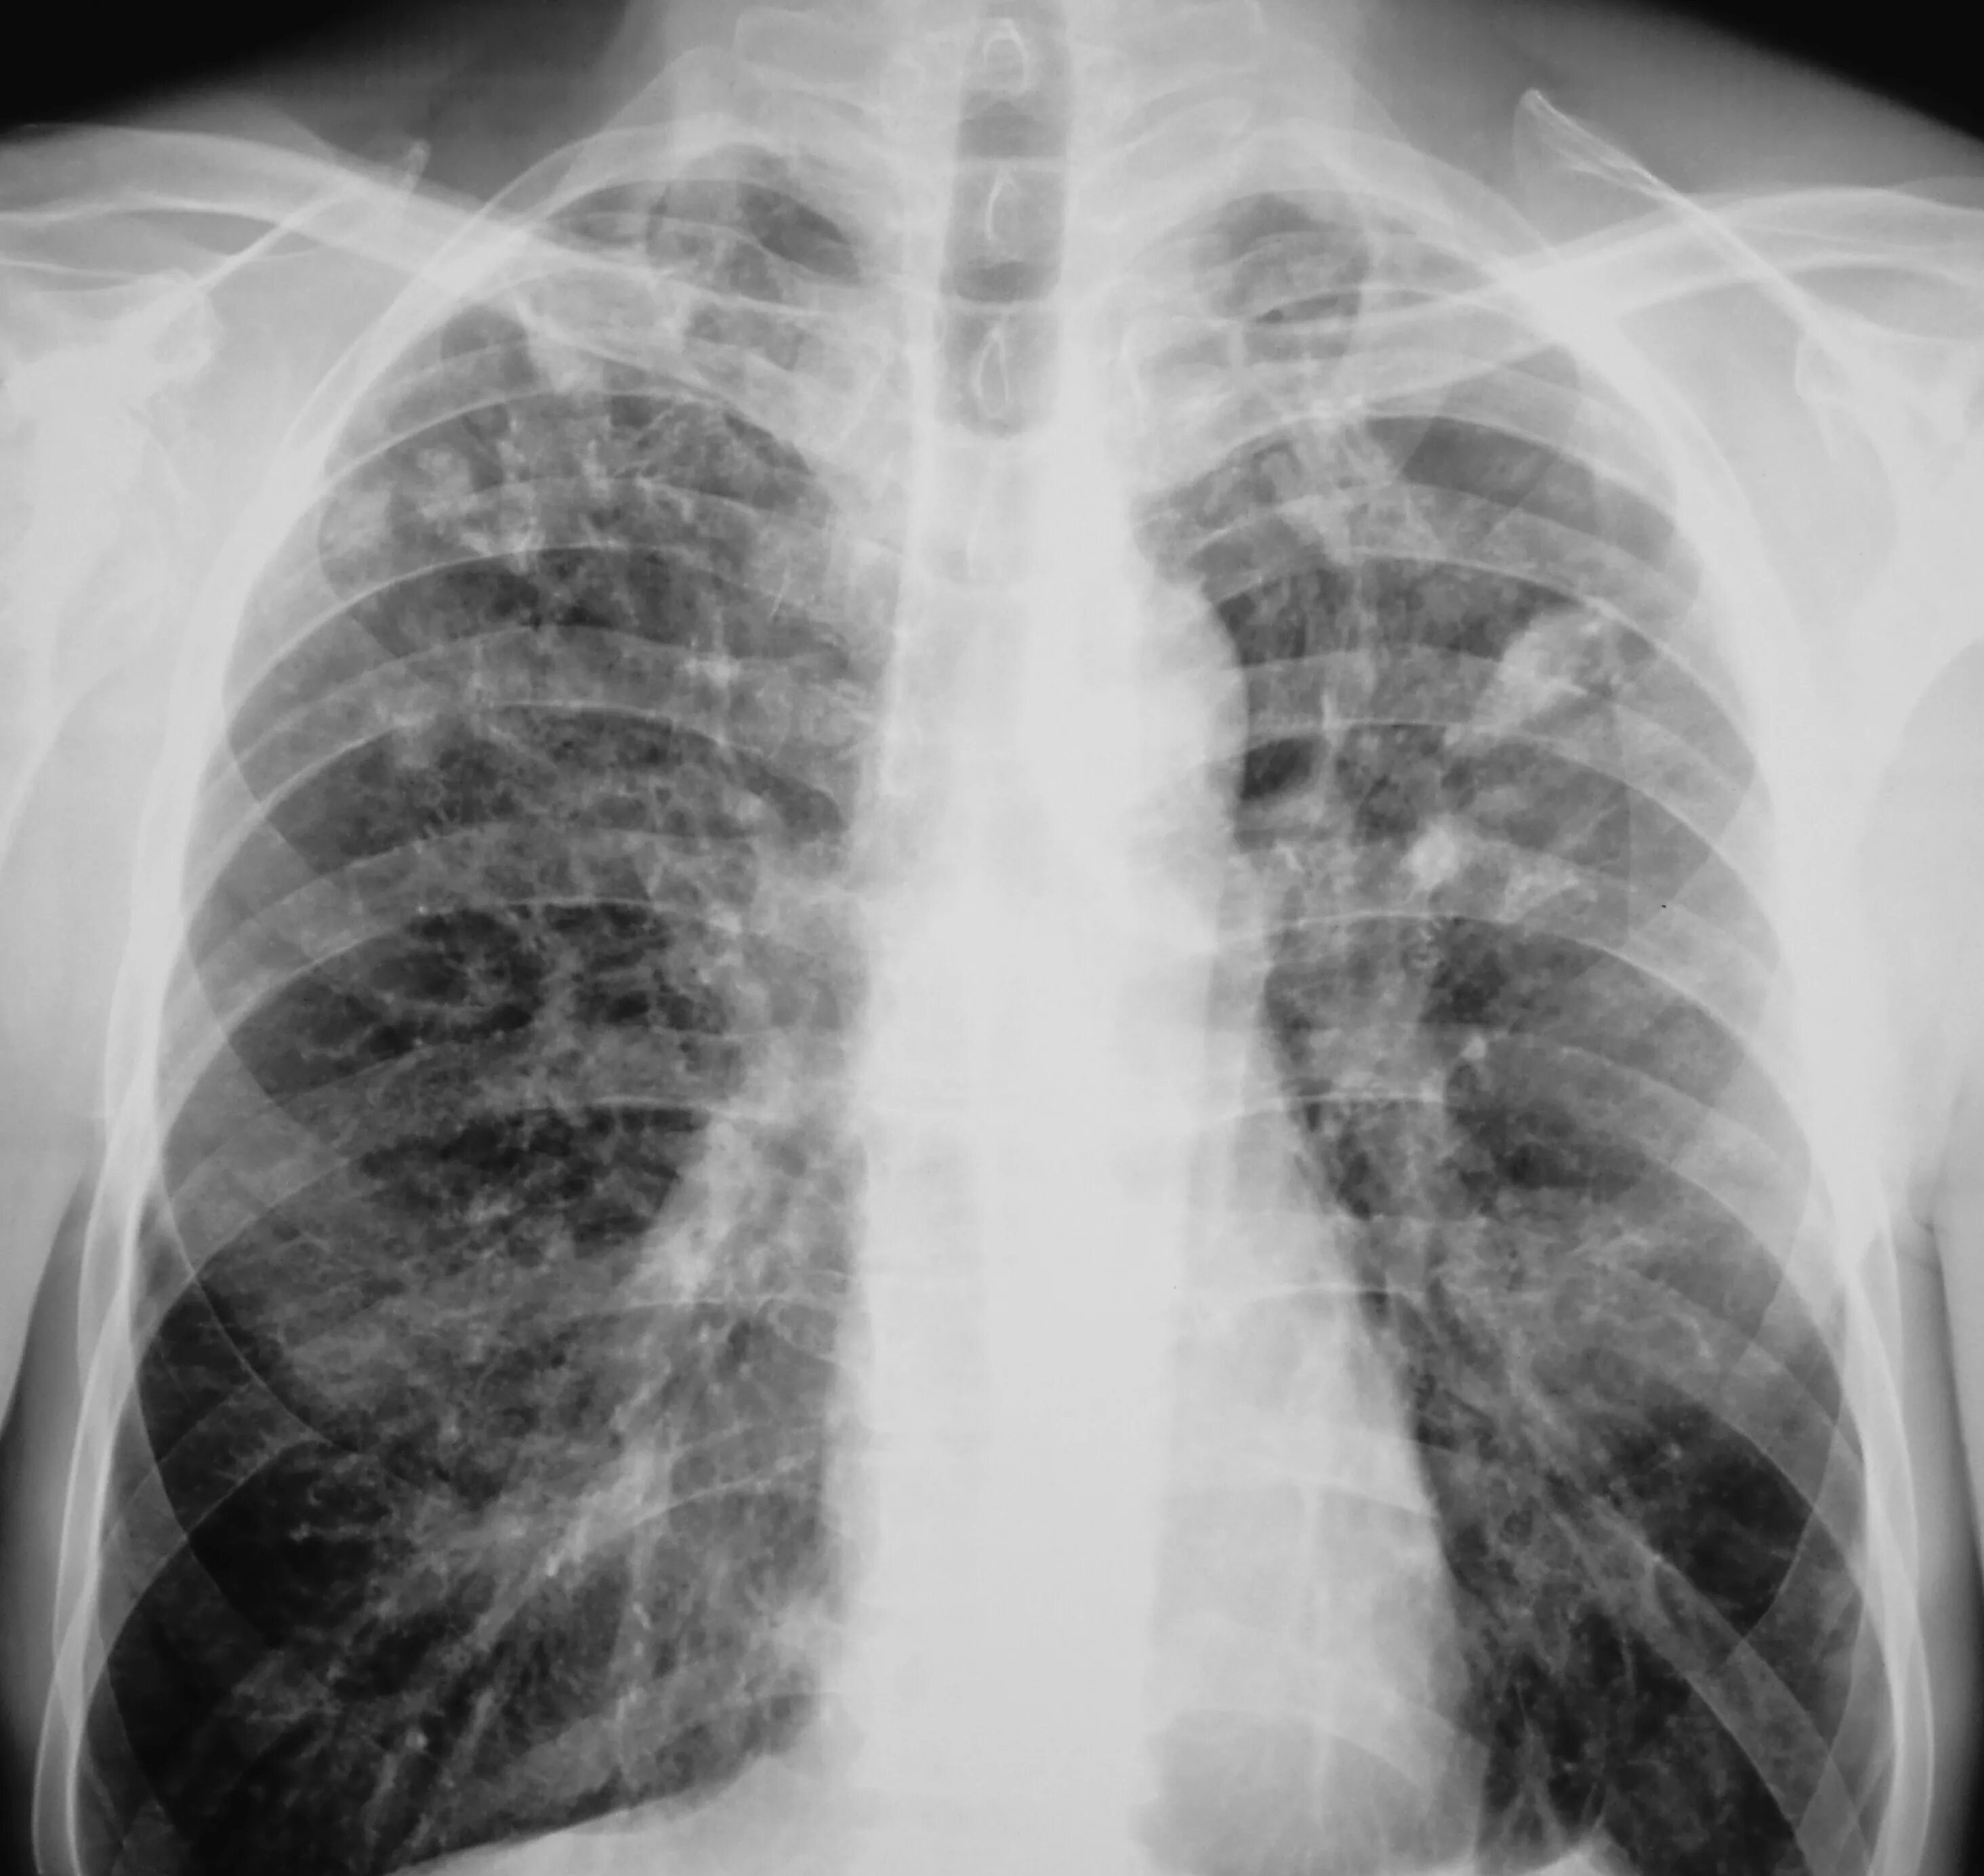

Лечится ли туберкулез у взрослых